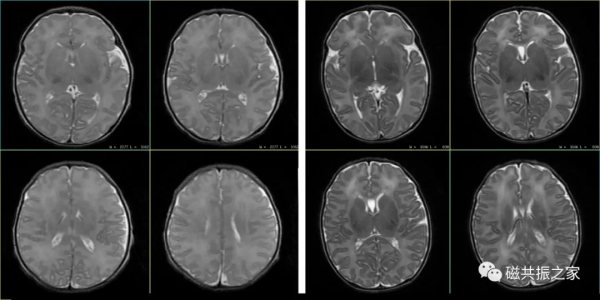

患兒4d,T2WI FSE△,1.5T。

左:TR=3100ms,TE=120ms。

右:TR=5200ms,TE=210ms。

對於嬰幼兒顱腦的掃描,特別是對於小於3個月的嬰兒,不管是T1WI還是T2WI,都應適當的延長TE和TR值,以獲得更好的影象信噪比和對比度,且掃描引數應根據磁場及掃描目的做出相應的調整。嬰幼兒隨著年齡的增長TR逐漸降低,通常至2週歲時與成人TR類似。